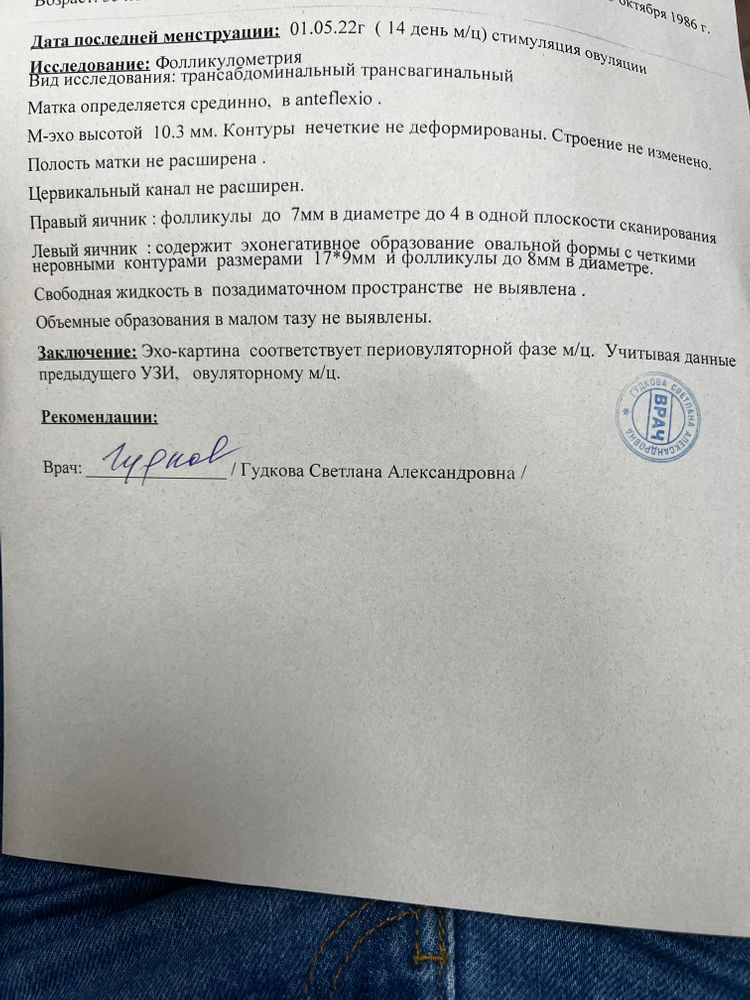

Всем доброго дня. Может ли быть такое, что сразу после овуляции (а может даже в момент) не будет свободной жидкости?

узист сказала может. И что похоже овуляция как раз вот она.

а Репродуктолог сказала, что нет. И скорее всего овуляция не произошла , а произошла лютеинизация.